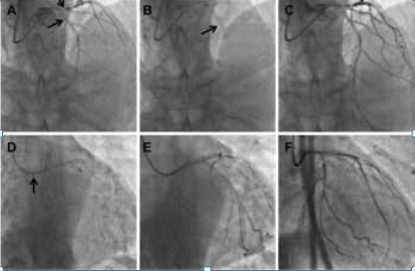

旋磨后左冠PCI 过程:(1)LAD 近- 中段旋磨后首先应用2.5 mm×20 mm 顺应性球囊扩张,16个大气压(atm), 但显示未充分扩张( 图2A,B), 再次选用2.5 mm×12 mm 非顺应性球囊扩张分别用29、30个atm 扩张,仍未扩张充分(图2C,D);(2)选用2.75 mm×12 mm 非顺应性球囊扩张分别用18、24 个atm 扩张,仍未扩张充分(图2E), 支架尝试不能通过;(3)考虑继续应用旋磨,旋磨头增大为1.5 mm,18 万转/分,20 s,共旋磨3 次(图2F);(4)旋磨后选用3.0 mm×12 mm 非顺应性球囊扩张用18 个atm 扩张,扩张基本充分(图2G);(5) LAD 近-中段成功置入2.75mm×30 mm 药物洗脱支架(DES)(图2H);(6)LCX 用2.5 mm×12 mm 非顺应性球囊扩张后顺利置入2.75 mm×18 mm DES(图2I);(7) LM-LAD 与LCX 之间采用Crush 术式,在LM-LAD 置入3.0 mm×14 mm DES(图2L);(8) LM-LAD和LCX 支架分别用3.0 mm×15 mm 和2.5 mm×12 mm,压力分别为12、10 atm 行对吻扩张(图2M);(9) 最后造影结果显示血流明显改善(图2N)。

图2 左冠脉球囊扩张和支架过程